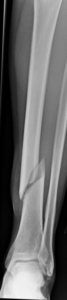

Tibia shaft fractures in adults can be treated by a variety of techniques depending on many factors. Some of these techniques might even be used in combination at times and include: casting, bracing, external fixation (where pins are inserted into the bone and connected to rods outside of the skin), plates and screws, and rods (also referred to as nails) placed inside the bone (Figure 1). The time it takes for a tibia shaft fracture to heal can vary greatly depending on the characteristics of the injury as well as patient factors. One of the most important modifiable patient factors that can delay healing in tibia fractures is tobacco/nicotine use. Nicotine use can significantly inhibit bone healing and a tibial shaft fracture is an excellent reason to stop smoking.

Fig 1. Tibia fracture treated with a rod and screws